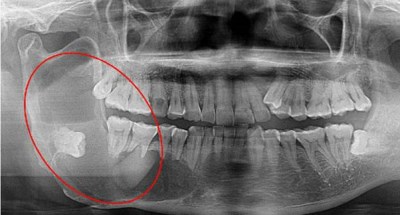

5).颌骨囊肿:低位埋伏阻生的智齿,有导致颌骨囊肿病变的风险。